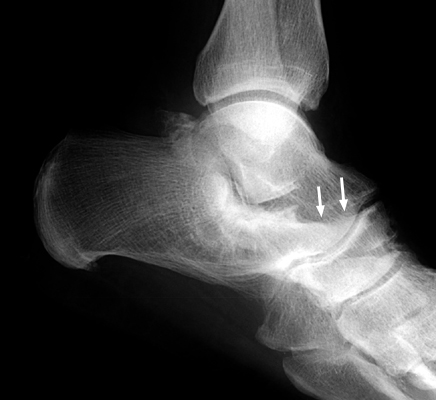

Calcaneonavicular coalition

Plain film and CT images of calcaneonavicular coalition. Notice the elongated, tubular like extension of the anterior calcaneus seen on the lateral film; this imagery has been likened to the elongated nose of an anteater. There is abnormal bony fusion of the calcaneus and navicular bones, with the presence of a bony bar extending between these two bones.

bulletOestreich AE, Mize WA, Crawford AH, Morgan RC Jr.: The "anteater nose": a direct sign of calcaneonavicular coalition on the lateral radiograph. J Pediatr Orthop 1987 Nov-Dec;7(6):709-1.          [See related articles]